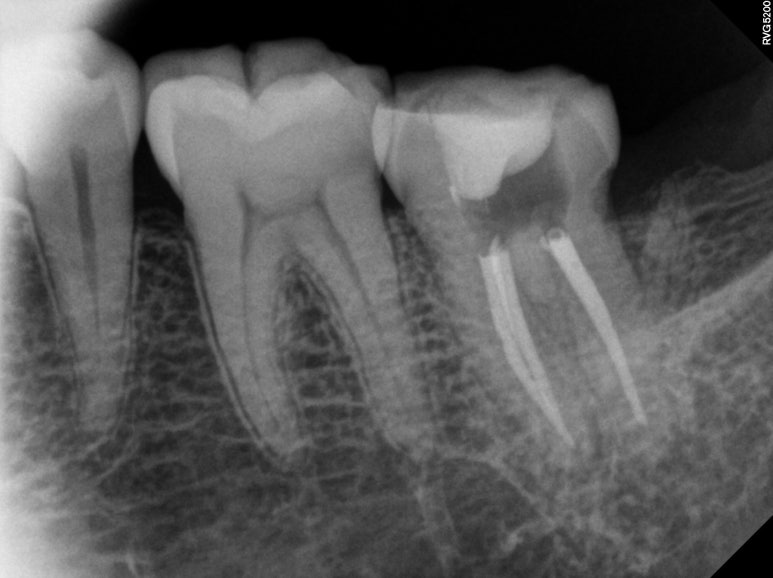

불편하다고 얘기하셔서 아까 파란색으로 표시했던 왼쪽 아래 어금니를 자세히 살펴보기 위해 치근단사진 촬영을 해보았습니다.

분명히 명확한 충치나 잇몸질환은 관찰되지 않았어요...

신경치료를 시작하기 위해 만들었던 입구를 통해, 세로로 형성된.. 그리고 오래되어 착색까지 된 진한 crack line을 관찰할 수 있었습니다.